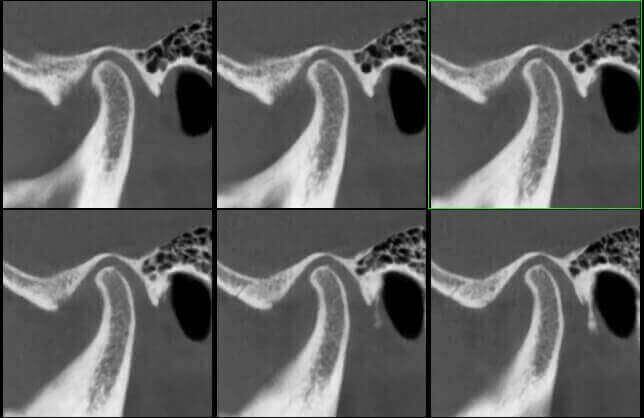

ATM Bocca Aperta

ATM Bocca Chiusa